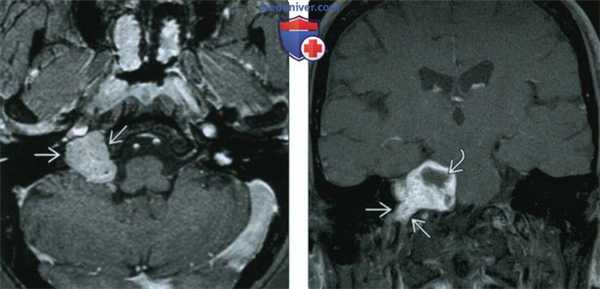

(Слева) На рисунке коронального среза показана крупная параганглиома яремного гломуса, возникшая в яремном отверстии; опухоль инфильтрирует соседние структуры основания черепа, она поглотила яремную вену и ЧН IX-XII.

(Справа) При МРТ Т1ВИ в корональной проекции определяется крупная параганглиома яремного гломуса, проросшая основание черепа и распространяющаяся вверх и латерально к наружному слуховому проходу. Обратите внимание на множественные «пустоты потока» из-за высокой скорости кровотока, характерные для параганглиомы. Параганглиома яремного гломуса - вторая по частоте опухоль височной кости.

(Слева) При MPT Т2 ВИ в аксиальной проекции определяется крупное новообразование, исходящее из яремного отверстия; в ткани образования определяются множественные «пустоты потока» вследствие высокой скорости кровотока. Такая картина помогает дифференцировать эту опухоль от других новообразований этой зоны. Также наблюдается экссудация в ячейки пирамиды височной кости, вызванная обструкцией евстахиевой трубы.

(Справа) Корональная МРТ Т1ВИ FS с КУ: контрастная параганглиома яремного гломуса, прорастающая основание черепа и распространяющаяся кверху и латерально к среднему уху и наружному слуховому проходу. Этот пациент 15 лет с мутацией SDHB находится в группе высокого риска развития агрессивной параганглиомы.